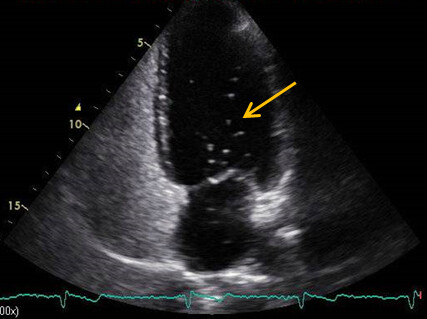

Hypermobiles Vorhofseptum

Im Rahmen der kardiologischen Untersuchung fiel echokardiografisch ein leicht hypermobiles Vorhofseptum auf (Abb. 1A). Im gepulsten Doppler (PWD) wurde dieser Bereich als unauffällig bewertet.

Abb. 1: Rechtsherz Echokardiografie, Credit: Perings